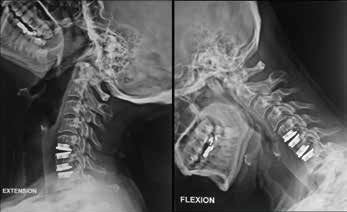

Cervical Multilevel